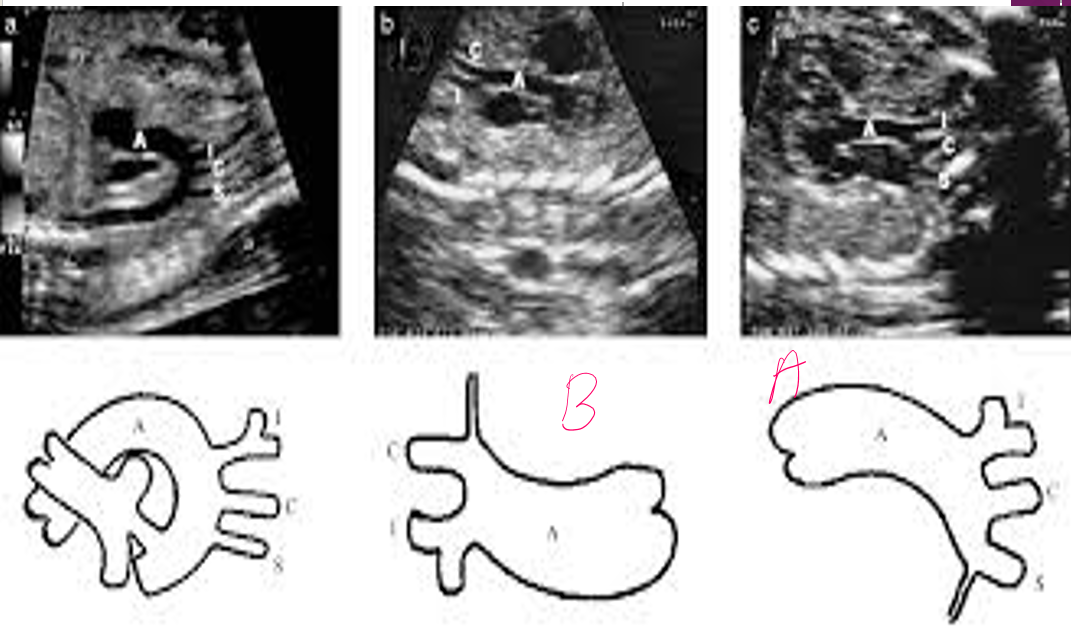

what are the types of coarctation?

A : ductal (juxtaductal)

B : preductal

C : post ductal

how is hemodynamics affected with each coarctation?

A & C : overload lungs (blood will go from ao → lig art → lungs)

B : deoxy blood going to LE (pulm art shunting deoxy blood to ao)